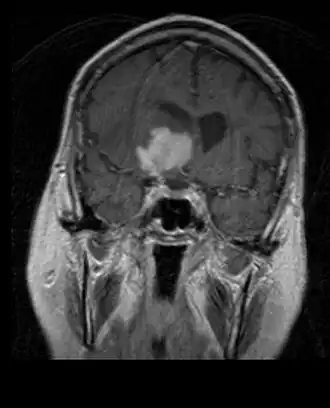

MRI toont meestal een enorme contrastverhogende laesie waarbij het cerebellum betrokken is. Zoals hierboven vermeld, heeft medulloblastoom een hoge neiging om lokaal de leptomeningen te infiltreren en zich ook door de subarachnoïdale ruimte te verspreiden, waarbij de ventrikels, cerebrale convexiteit en leptomeningeale oppervlakken van de wervelkolom betrokken zijn. Daarom is het noodzakelijk om de gehele craniospinale as in resonantie te brengen.

Medulloblastoom is de meest voorkomende kwaadaardige hersentumor bij kinderen. De hoogste incidentie komt voor bij kinderen in de leeftijd van 2 tot 7 jaar. Het grootste risico op ziekte blijft in de kindertijd, aangezien medulloblastoom zeer zeldzaam is bij mensen ouder dan 21 jaar.

Deze tumor is typerend voor de achterste fossa, waar hij is gelokaliseerd in beide hemisferen van het cerebellum of in de cerebellaire vermis. Omdat het invasief en snelgroeiend is, verspreidt het zich gewoonlijk naar andere delen van het centrale zenuwstelsel (CZS) via het CSF en kan het de bodem van het nabijgelegen vierde ventrikel en de hersenvliezen infiltreren. Meer zelden kunnen aanvullende CZS-metastasen optreden. Wanneer de maligniteit optreedt, omvatten de symptomen verlies van evenwicht, coördinatiestoornissen, diplopie, dysartrie en als gevolg van betrokkenheid van de vierde ventrikel, wat vaak resulteert in obstructieve hydrocephalus, hoofdpijn, misselijkheid en braken, en onstabiel lopen.

Het doel van de operatie is om zoveel mogelijk van de door de laesie gepresenteerde massa te verwijderen. In feite resulteren postoperatieve resterende tumoren in een slechtere prognose. Ook een voorbode van een ongunstige prognose is de aanwezigheid van tumorcellen in het hersenvocht of de resonantiedetectie van leptomeningeale metastasen. Een operatie alleen is meestal niet genezend. In sommige gevallen kan echter therapeutische bestraling van de craniospinale as, gericht op de primaire tumorplaats, het gevolg zijn. Het toevoegen van chemotherapie na bestralingstherapie verhoogt het genezingspercentage. Op platina gebaseerde geneesmiddelen (cisplatine of carboplatine), etoposide en een alkyleringsmiddel (cyclofosfamide of lomustine) worden samen met vincristine gebruikt. Met de juiste behandeling variëren de gevallen met een lange overleving van meer dan 3 jaar bij patiënten met medulloblastoom van 60 tot 60 jaar en 80 procent.